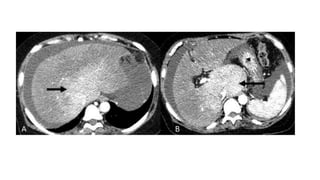

• #7 nodular surface (arrow) in the left lobe of liver. Volume redistribution in the form of caudate lobe hypertrophy

• #13 Axial venous phase images of contrast enhanced CT (A) right posterior hepatic notch sign and (B) volume redistribution with widened porta hepatis.